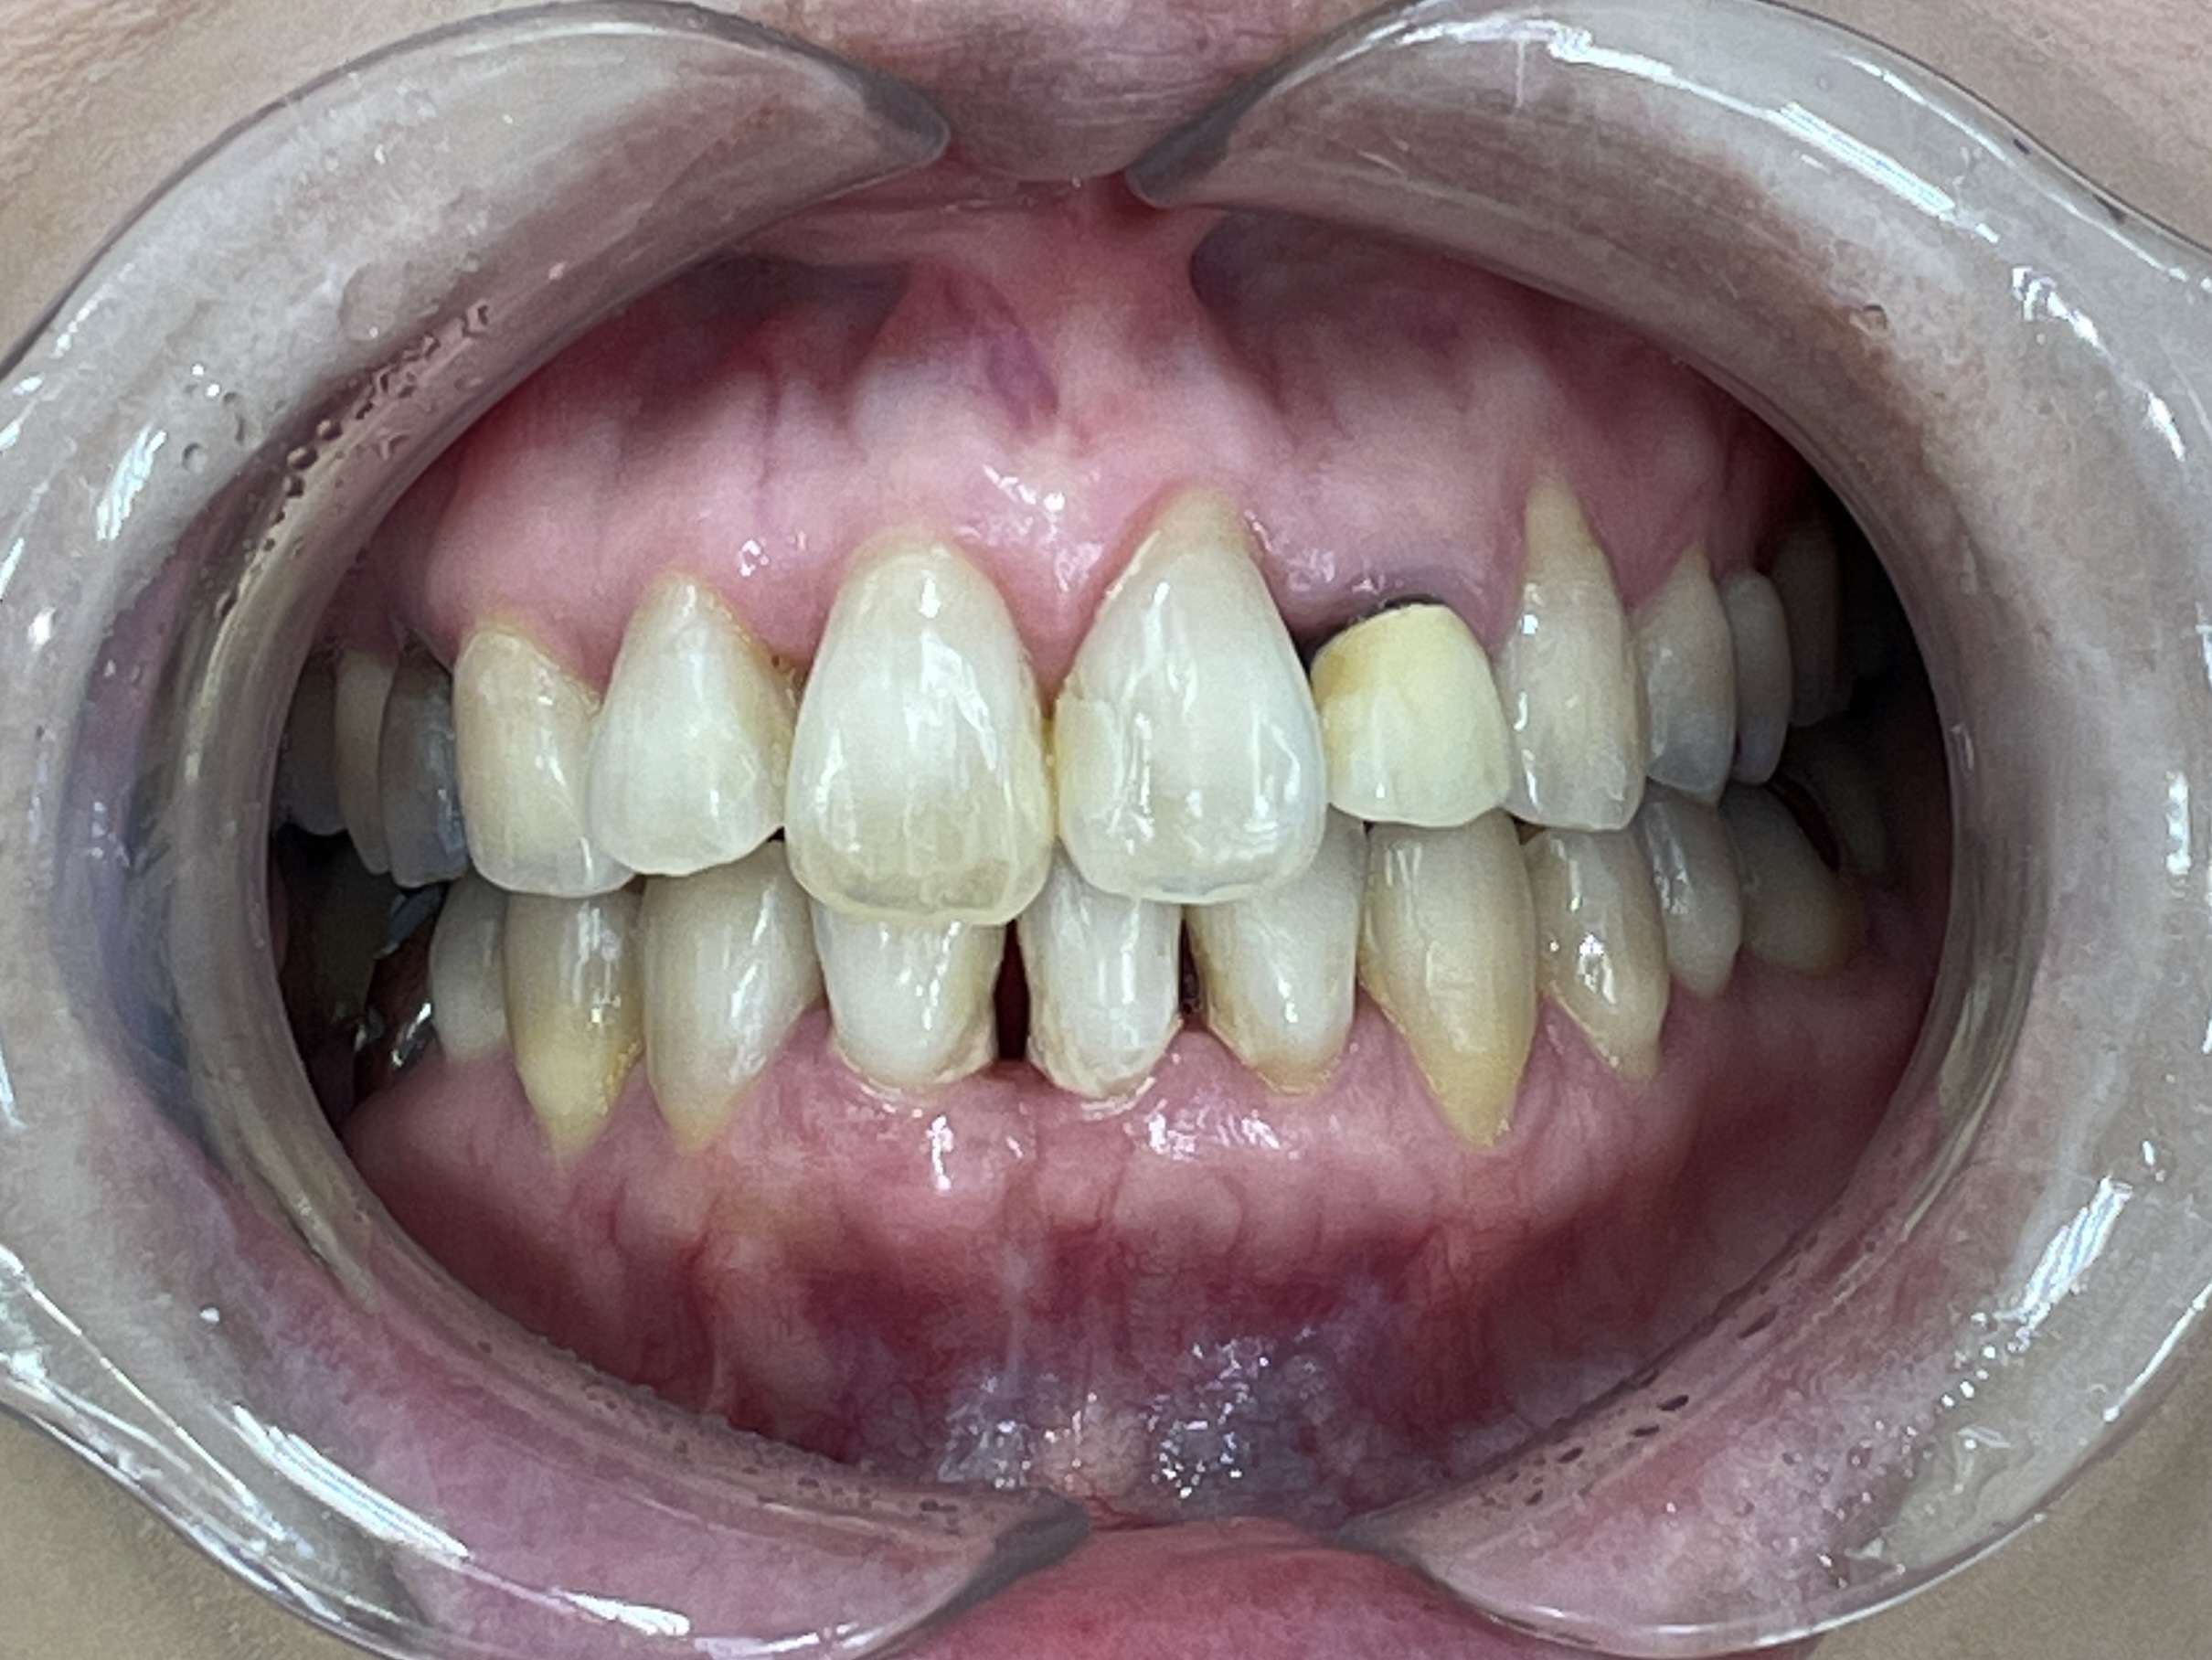

歯が正しい位置に並び、噛み合わせも改善しました。

患者様にも「きれいな歯並びになって嬉しい。歯磨きもしやすくなった」と大変お喜びいただきました。